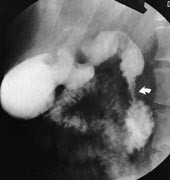

Pasient 1. En 19 år gammel kvinne hadde hatt magesmerter i noen år. Smertene ble kraftig forverret i forbindelse med diaré som oppstod etter en Syden-tur. Det tilkom amylasestigning til knapt 1 000 U/l, og peroralt inntak av annet enn vann provoserte frem magesmerter og brekninger. Røntgenundersøkelse av ventrikkel og duodenum viste en 2 – 3 cm lang stenose i nedadstigende del av duodenum (fig 2). Motiliteten i ventrikkelen var nedsatt, og det forelå retensjon i ventrikkel og øvre del av jejunum. Stenosen ble bekreftet ved gastroskopisk undersøkelse. CT av øvre del av abdomen med vann som peroralt kontrastmiddel (fig 3) viste en kort stenose i midtre nedadstigende duodenalavsnitt, hvor duodenum var omsluttet av smålobulært pancreasparenkym. Pancreas for øvrig var upåfallende. Magesekken var distendert etter vanninntaket, og distensjonen omfattet også duodenum proksimalt og distalt for stenosen. Pasienten responderte på total parenteral ernæring. Amylasen normaliserte seg. Ved utskrivning kunne pasienten spise normalt. Det ble antatt at pankreatitt i den annulære pancreas forbigående hadde gitt en høy gastrointestinal obstruksjon.

Slimhinnen er vanligvis normal. Pylorusinkompetanse og reversert peristaltikk kan forekomme (2, 7). Nyere radiologiske metoder kan diagnostisere den annulære pancreas. Ved CT kan selve annulus fremstilles i form av normalt pancreasvev som helt eller delvis omslutter andre del av duodenum (fig 3). Lavattenuerende peroralt kontrastmiddel (vann) og jodholdig kontrastmiddel intravenøst, som ble brukt hos aktuelle pasient (fig 3), er best for å fremheve kontrasten mellom duodenallumen og kontrastoppladende pancreasvev (2). Jod- eller bariumholdig kontrastmiddel i duodenum vil imidlertid kunne benyttes for å påvise selve det stenotiske tarmsegment inne i det tilsynelatende forstørrede pancreashodet (7). Hos aktuelle pasient var den del av duodenum som lå omsluttet av pancreashodet, ikke distendert av vannet. Anomalien kunne likevel diagnostiseres, da man i CT-snittene umiddelbart ovenfor og nedenfor pancreasringen så en dilatert duodenum som gradvis fikk et mer medialt forløp enn normalt og som smalnet av for å passere gjennom høyre del av pancreashodet. Like kaudalt for pancreashodet utvidet duodenum seg igjen. Vanligvis er stenosen minst 2 cm lang, og CT er derfor velegnet for å stille diagnosen, da det ved undersøkelse av pancreas benyttes kontinuerlige, maksimalt 5 mm tykke snitt. CT bør være førstevalg som metode pga. liten invasivitet og høy tilgjengelighet. Vanlig ultrasonografi vil også kunne gi mistanke om lidelsen ved funn av utspilt, væskefylt prestenotisk duodenum.